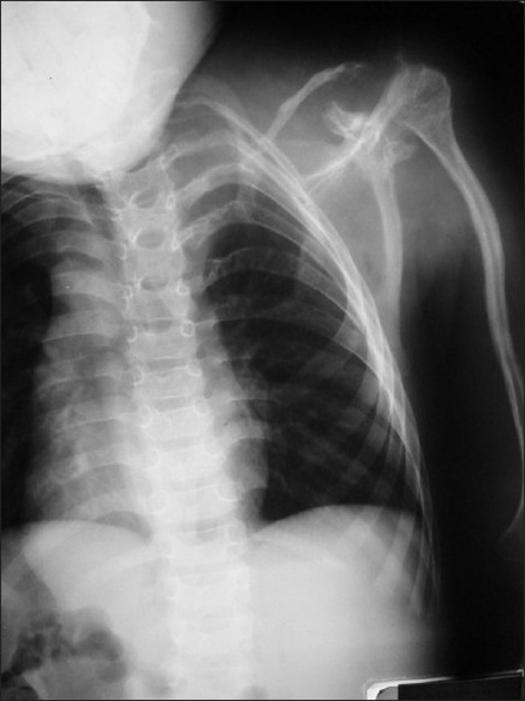

This is a case report of an eight-year old boy with neurofibromatosis and a 120 degrees dystrophic kyphosis of the cervical spine. He presented with progressive quadriparesis caused by spondyloptosis of the C2/C3, and was successfully treated by skull traction and one-stage anterior fibular strut graft lying between the tubercle of the atlas through the C2 body slot and lower vertebrae. At seven years follow-up there was, loosening of lower vertebral screws which allowed growth and residual mobility of lower vertebral joints while the fusion of upper cervical spines was still solid.

https://cdn.ncbi.nlm.nih.gov/pmc/blobs/628c/2822428/386cf2fc9ea1/IJOrtho-44-95-g001.jpg